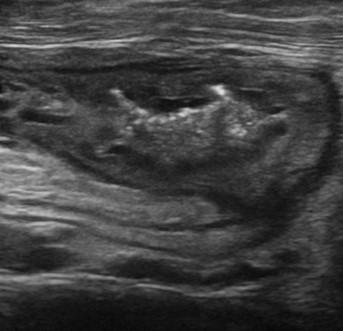

Viêm ruột

» Thông tin: Nữ giới – 55 tuổi.

» Lâm sàng: Tiêu chảy.